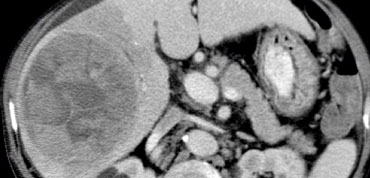

Large HCC with mozaik pattern in a non cirrhotic patient. Large HCC with mozaik pattern in a non cirrhotic patient.